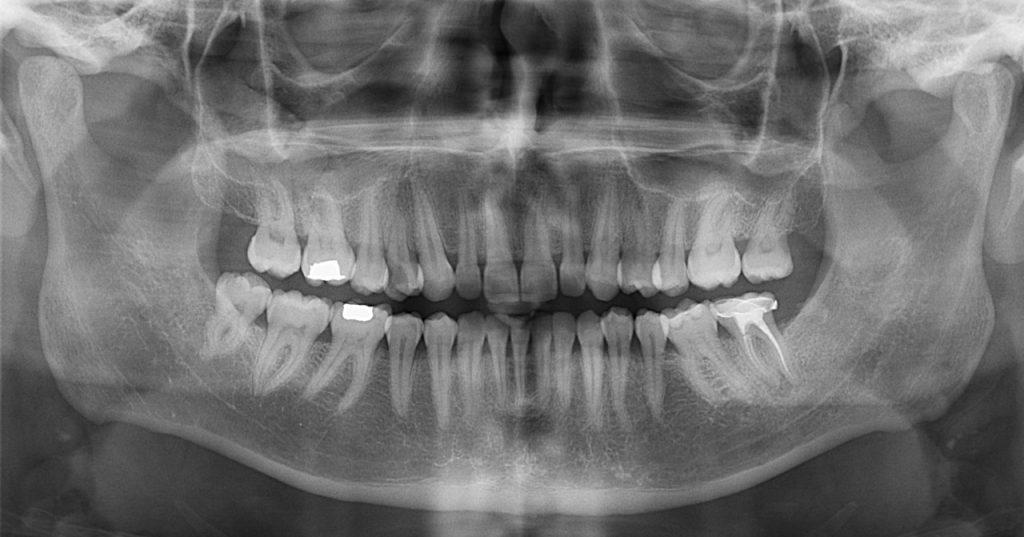

Imágenes panorámicas de alta resolución para una visión integral.

Contamos con equipos digitales de rayos X de última generación, que permiten obtener estudios extraorales precisos, rápidos y con excelente definición. Estas imágenes son clave en ortodoncia, cirugía, ATM y otras especialidades.

• Panorama Digital (OPG)